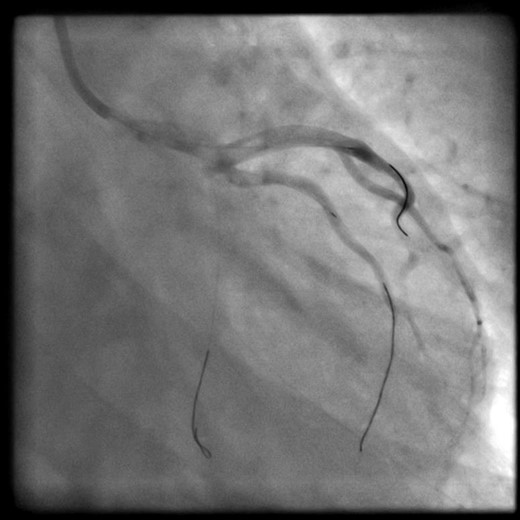

At the beginning of the procedure, the left main stem was engaged, however dampened pressure was noted and a test shot showed left main stem occlusion with dissection (Fig. 1).

Test shot showing left-main-stem occlusion with dissection (National-Heart-Lung and Blood-Institute class F).